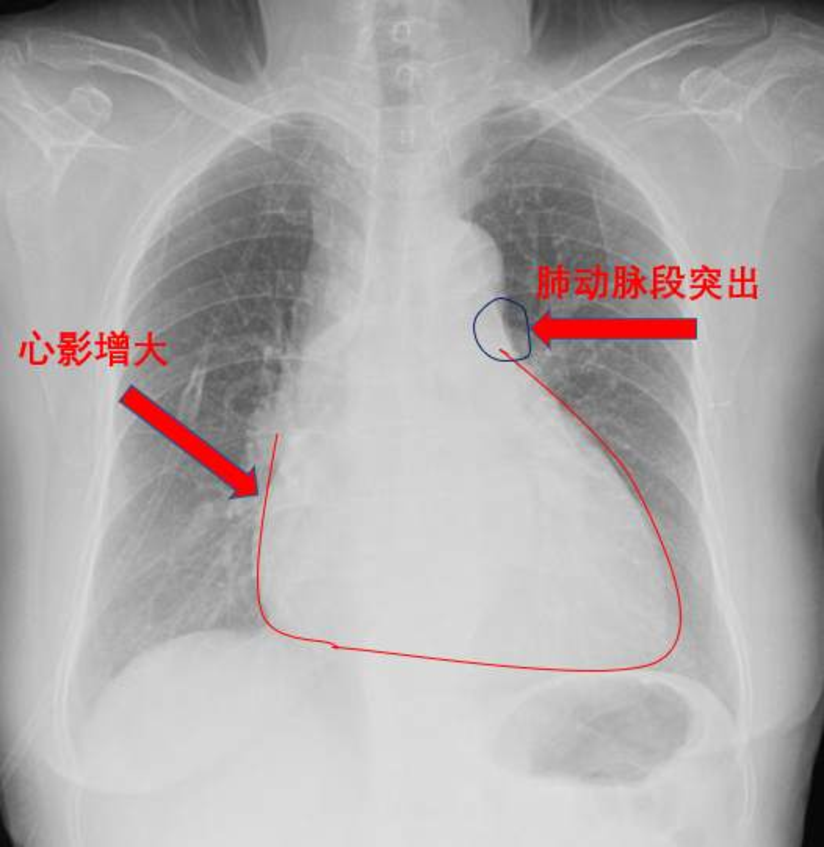

下肢静脉彩超提示双侧小腿多支静脉血管血栓形成。心超彩超示重度肺动脉高压(肺动脉收缩压101mmHg),右心明显增大,TAPSE:1.68cm,少量心包积液(图2)。肺动脉CT(CTPA)示主肺动脉及右肺动脉干明显增宽,右肺动脉干见巨大充盈缺损,叶、段肺动脉均未显影;左侧肺动脉多发分支充盈缺损(图3)。肺动脉造影提示右肺动脉叶段分支均未显影(图4)。

图2心超 图3